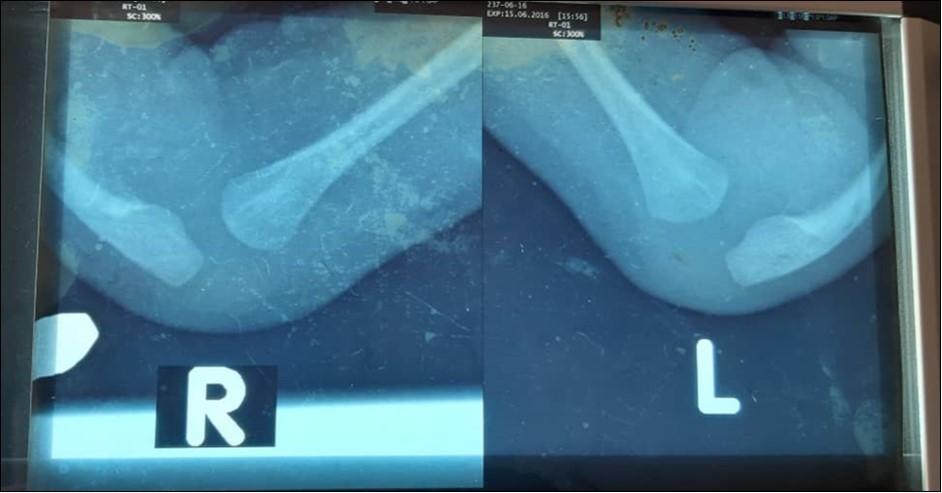

Physical examination revealed a young infant who was active. Both forearms were shortened and bowed ulnarwards. There was severe radial deviation at both wrists. There were no abnormalities detected in other systems. X-ray confirmed bilateral Bayne type IV deformity, Figure 1. Complete blood count was normal.

Figure 1.Depicts pre-operative radiographs of the forearms of the infant showing bilateral absence of the radius